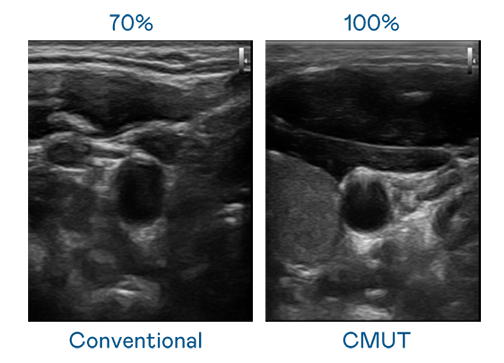

CMUT 技术是一种用电容式微机电元件来产生超音波讯号的技术。与传统 PZT 压电式技术相比,CMUT 频宽增加 30%,更宽频的超音波讯号让影像解析度大幅提升,是实现高影像品质医疗超音波扫描、促进精准医疗发展的关键技术。

超音波影像的解析度高低,首先取决于探头能发出的讯号频宽。金年会官方网站入口 CMUT 可提供高清晰的超音波讯号,提供高频宽、高灵敏度、影像纹理细节更高的超音波影像,协助医护人员缩短影像判读时间及利用精准的医疗影像进行诊断。